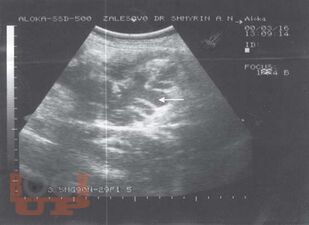

Ультразвуковая диагностика заболеваний толстой кишки

Шмырин А. Н. Ультразвуковая диагностика заболеваний толстой кишки : атлас / А. Н. Шмырин. - М. : Медпрактика-М, 2007. - 48 c. - ISBN 9785988030959. - Текст : электронный // ЭБС "Букап" : [сайт]. - URL : https://www.books-up.ru/ru/book/ultrazvukovaya-diagnostika-zabolevanij-tolstoj-kishki-3675620/ (дата обращения: 22.04.2026). - Режим доступа : по подписке.

Атлас представляет собой учебное пособие для начинающих специалистов и всегда доступный справочник для профессионалов. Форма компоновки материала позволяет быстро получить иллюстрацию патологического процесса и его описание.

Атлас рассчитан на специалистов по ультразвуковой диагностике, проктологов, гастроэнтерологов.